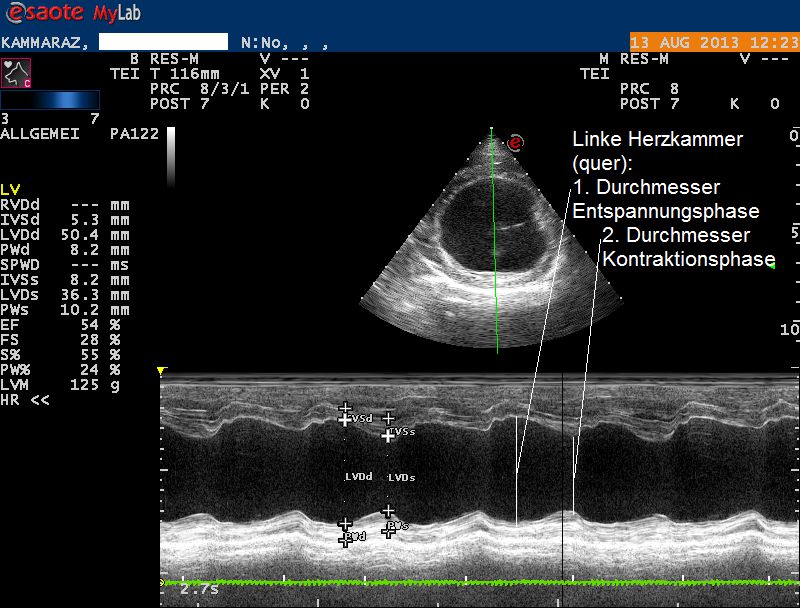

Der Herzultraschall bestätigt den röntgenologischen Verdacht eines Herzproblems: Sowohl die Hauptkammer als auch der linke Vorhof sind bei Karammaz stark erweitert; die Kammer zieht sich ausserdem in der Pumpphase des Herzen zu wenig zusammen, wodurch das Organ zuwenig Blut fördern kann. Im Doppler-Ultraschall ist zu erkennen, dass durch die Erweiterung des Herzen auch die Klappen zwischen linkem Vorhof und linker Kammer undicht geworden sind und Blut beim Pumpen zum Teil nicht in den Körper, sondern zurück in den Vorhof gepumpt wird. Sonografisch ist also ein typisches Bild einer sogenannten Dilatativen Cardiomyopathie (DCM, Herzmuskelerkrankung, welche mit einer Erweiterung einhergeht) vorhanden; als Folge der geringen Pumpleistung des Herzen hat sich ausserdem ein Lungenödem gebildet.